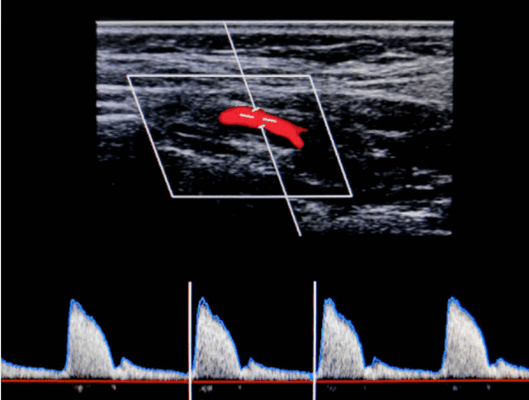

Оценка нормальной подключичной артерии производят многофазный сигнал высокого сопротивления допплеровских сигналов, то есть трехфазный. Цветной допплеровский поток от подключичной артерии будет отражать высокое периферическое сопротивление. Приток крови будет к датчику в пике систолы, а дальше от датчика в начале диастолы и к датчику в конце диастолы. Если возникает значимый стеноз или окклюзия проксимального сегмента сосуда, то допплеровский сигнал дистальнее стеноза будет монофазный. Разница артериального давления на руках более 20 мм рт. ст. обычно связаны с заболеванием подключичной или безымянной артерии на стороне с более низким кровяным давлением.

После того, как бифуркация и ее ответвления были идентифицированы и при условии отсутствия областей значительного заболевания, эффективное исследование состоит в том, чтобы провести измерения пиковой систолической скорости в общей сонной артерии, внутренней сонной артерии и наружной сонной артерии, чтобы иметь полный протокол осмотра. Данные получают с использованием спектрального допплера от общей сонной артерии (ОСА) на 2-3 см ниже бифуркации; внутренняя сонная артерия на 1-2 см выше луковицы или настолько высоко, насколько это возможно, чтобы исчезла нормальная бульбарная турбулентность, также измеряют скорость в наружной сонной артерии. Для обычных измерений контрольный объем устанавливается примерно на одну треть от общего диаметра и помещается в центр сосуда, чтобы избежать естественной турбулентности на краю просвета и «удара стенки» из-за включения стенки сосуда в контрольный объем.

Угол импульсно-волнового допплера при исследовании поддерживается как можно острый, в идеале, в диапазоне 45-60 градусов. Это хорошая практика, когда врач пытается придерживаться определенного угла, например 55 или 60 градусов, чтобы улучшить воспроизводимость результатов между исследованиями. При значительных стенозах лучше уменьшить размер контрольного объема, поскольку это позволяет лучше определить площадь пика сигнала систолического потока. Цветовой допплер позволяет более точно оценить направление потока при стенозе, поскольку он не всегда может быть параллельно стенкам сосуда. Точное окончательное местоположение объема выборки кровотока выбирается с использованием комбинации звукового доплеровского сигнала и спектра таким образом, чтобы получить наиболее чистый, высокочастотный звуковой сигнал и наилучшую спектральную трассу. При стенозах контрольный объем следует перемещать по длине стенотического сегмента, чтобы определить местоположение пикового сигнала. Усиление для спектрального дисплея должно быть настроено на использование полной шкалы серого без чрезмерного или недостаточного насыщения.